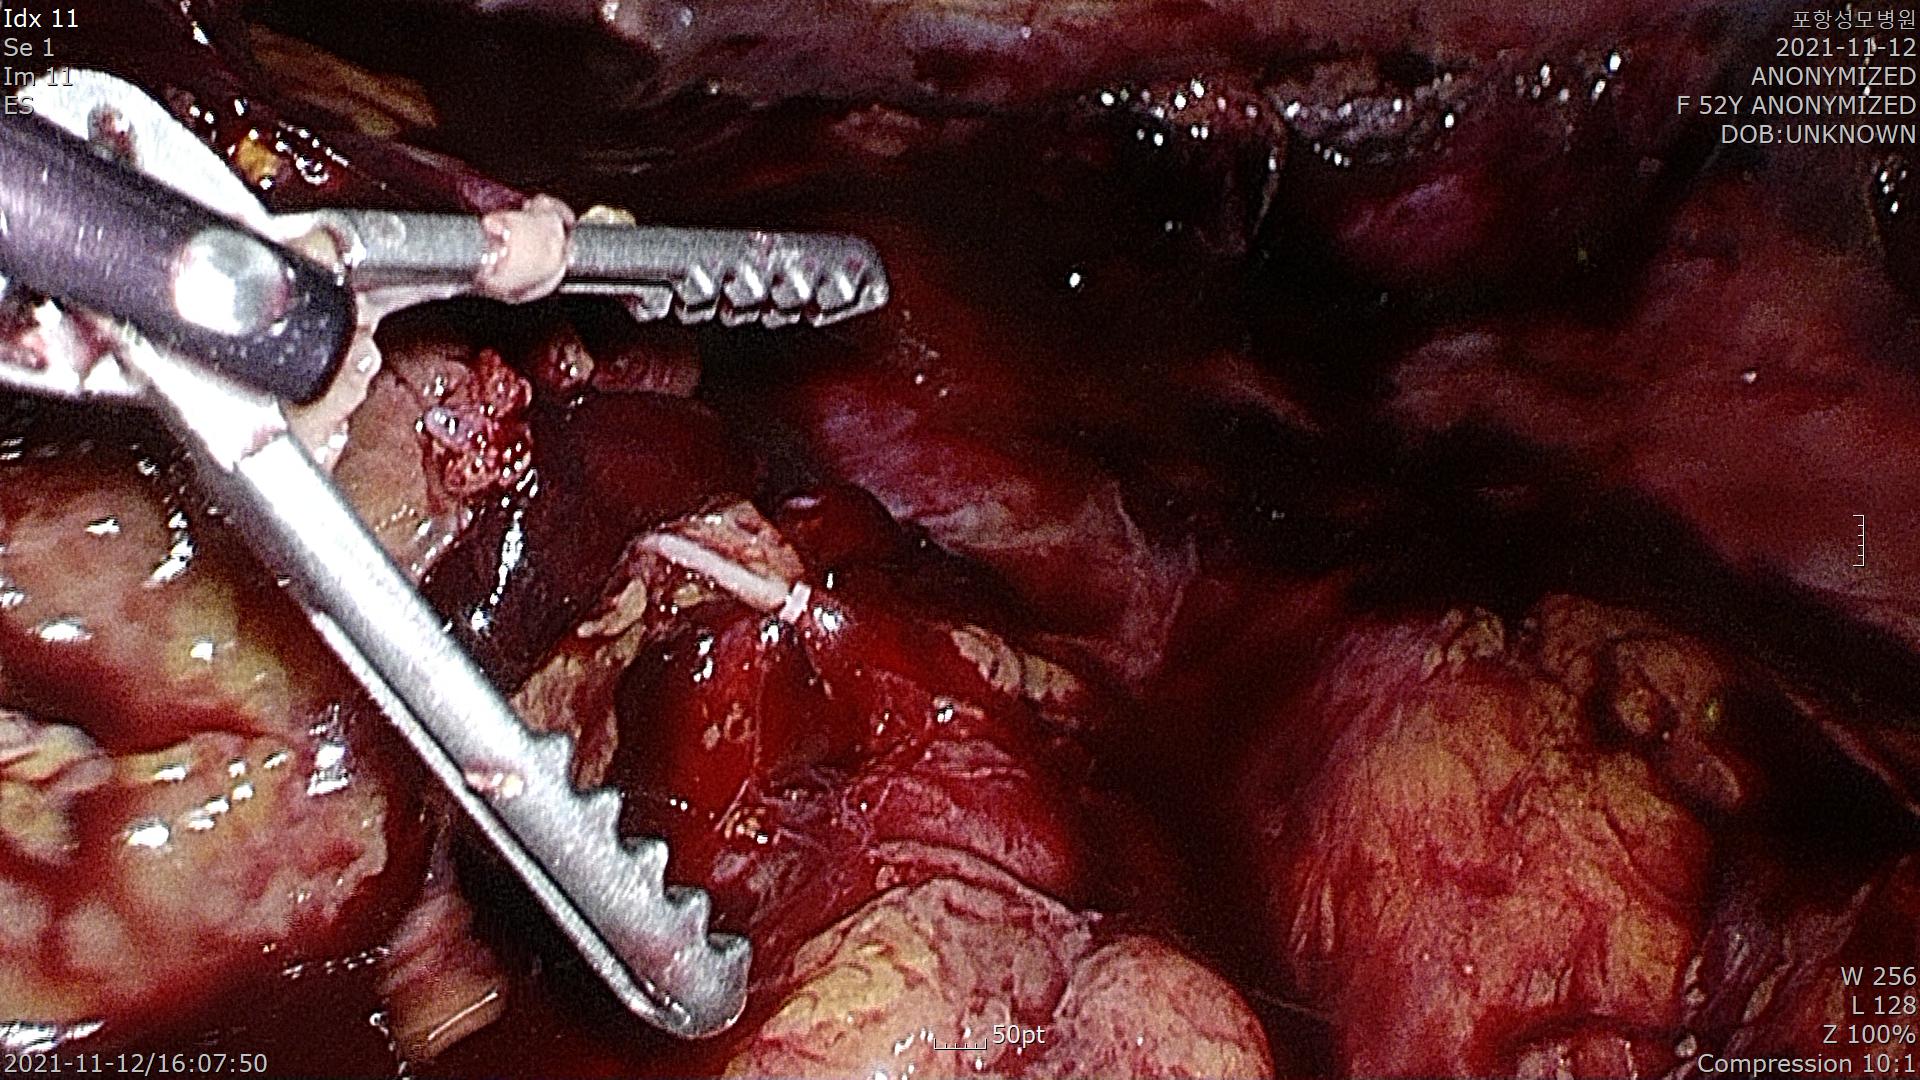

좌측에 비장이 확인되고 비장에서 출혈이 심할 수 있기 때문에 조심스럽게 박리합니다.

낭종이 사이즈가 커서 흡인을 시행하고 들고 있는 모습입니다.

낭종을 공급하는 혈관을 클립으로 잡은 모습입니다.

낭종을 제거하고 작은 구멍으로 빼내야 하기 때문에 여러 조각으로 분리되었습니다.

수술은 잘 끝났고 110분 걸렸습니다.